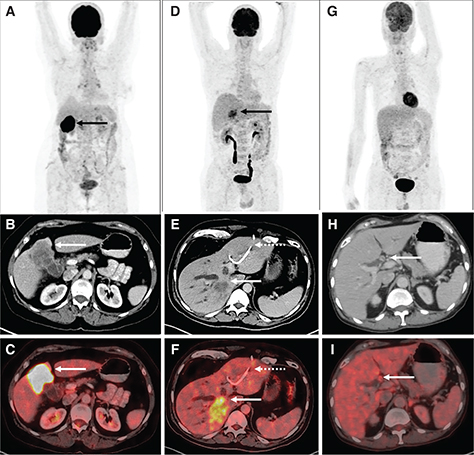

Detection of primary HCC using 18F-FDG PET/CT alone is limited, with a relatively low sensitivity (approx. 50–65%) compared to current standard of care imaging. Higher grades of HCC (less differentiated) tend to have higher FDG avidity, whereas well-differentiated HCC shows relatively low 18F-FDG uptake (3). This results from the varied expression of glucose transporters (GLUT) and increased glucose-6-phosphatase activity in well differentiated HCC while poorly differentiated HCC has loss of glucose-6-phosphatase activity. In a study by Torizuka et al., the degree of differentiation of HCC was correlated with 18F-FDG uptake, with higher-grade tumors showing twice FDG uptake compared to lower-grade tumors (4). Dual point imaging can be performed, in addition to the conventional imaging 1-hour after FDG injection, to increase the sensitivity of 18F-FDG PET/CT to detect HCC (5). Figure 1 shows 18F-FDG PET/CT findings in primary HCC.

Fig 1

Figure 1. 18F-FDG PET/CT in HCC. A. Maximum Intensity Projection (MIP) image of 18F-FDG PET/CT in a patient with well-differentiated HCC shows no abnormal increased tracer uptake in the liver. Corresponding CT (B) and fused PET/CT (C) images for the same patient show non-FDG avid arterially enhancing lesion in segment VIII of liver, consistent with primary HCC (white arrows). D. Maximum Intensity Projection (MIP) image of 18F-FDG PET/CT in a patient with poorly differentiated HCC showing areas of increased FDG uptake in the liver. Corresponding CT (E) and fused PET/CT (F) images in the second patient show FDG avid (SUVmax 9.4) arterially enhancing mass involving the segments VI and VII of liver (yellow arrows).